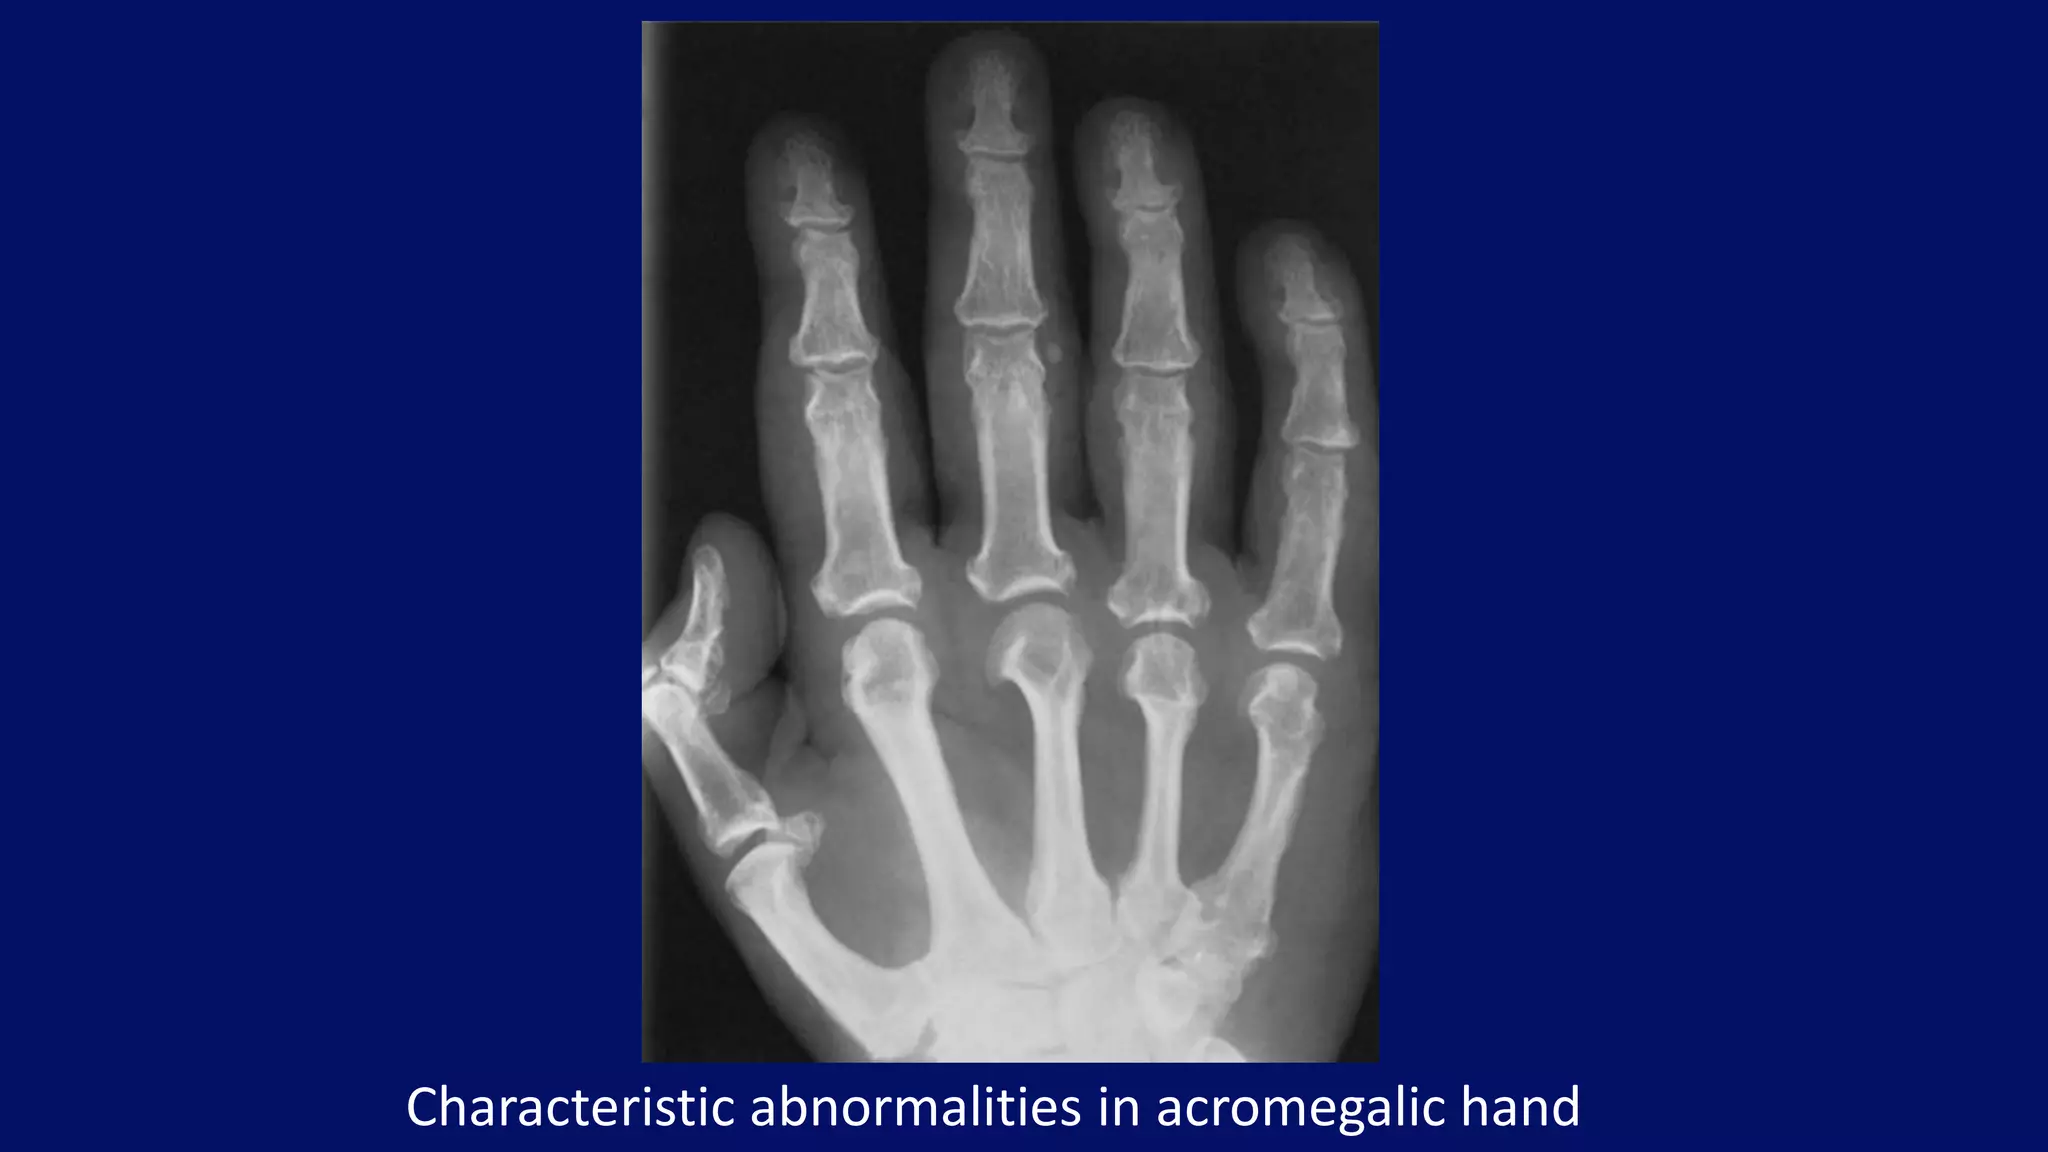

Characteristic abnormalities in acromegalic hand

Acromegalic osteoarthritis

Acromegaly • beak-like osteophytes

• Spade phalanx sign

• #96 Dorsovolar radiograph of both hands of a 42-year-old man with acromegaly shows widening of some and narrowing of other joint spaces, enlargement of the distal tufts and the bases of terminal phalanges, and beak-like osteophytes affecting particularly the heads of the metacarpals. Note the soft tissue prominence and the large sesamoid bones at the first metacarpophalangeal joints. The sesamoid index (derived by multiplying the vertical and horizontal diameters of the sesamoid bone) is 48 in this patient; normally, it should not exceed 20 to 25.

• #97 Acromegalic arthropathy. Characteristic abnormalities in acromegalic hand include prominence of the soft tissue, enlargement of the tufts and bases of the distal phalanges, widening of the metacarpophalangeal joints, and beak-like osteophytes at the radial aspect of the metacarpal heads (metacarpal hooks). Note also markedly enlarged sesamoid bone at the first metacarpophalangeal joint.